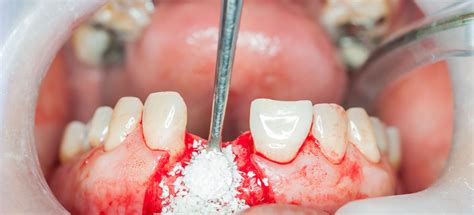

- Procedimiento quirúrgico: se realiza una incisión en las encías, se coloca el injerto y se cierra la zona tratada. A continuación, se procede a la cirugía mediante anestesia local. Se injerta un bloque de hueso y se ancla mediante tornillos de titanio.

En la cirugía ósea guiada se cubre todo el espacio de hueso perdido con el material de injerto.